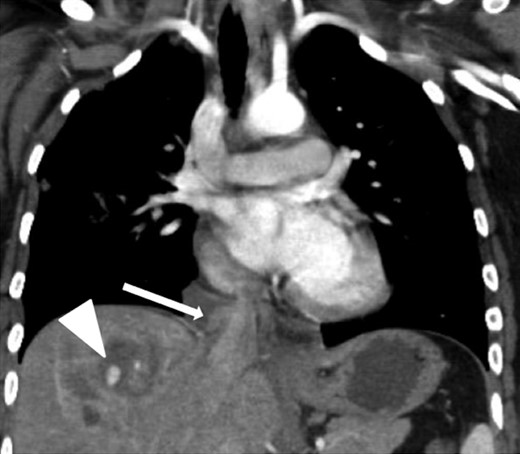

Coronal contrast-enhanced CT of the chest showing abnormal contour of the supradiaphragmatic IVC with ventrally and laterally confined contrast extravasation (arrow) consistent with a pseudoaneurysm surrounded by pericaval hematoma as well as a segment 8 hepatic hypodensity consistent with liver laceration and focal area of contrast extravasation (arrowhead).